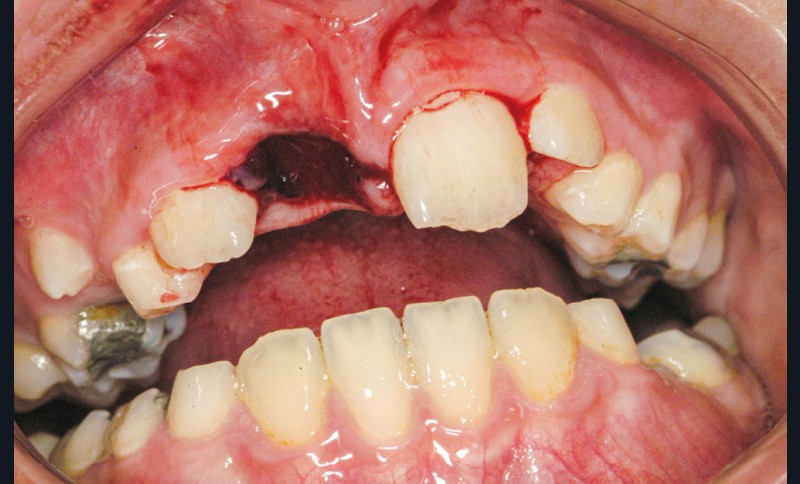

Enfant de 9 ans dont une incisive centrale maxillaire a été expulsée en jouant au football. Appel immédiat de la mère à qui l’on conseille de conserver la dent expulsée dans du sérum physiologique (fig. 1). Le temps extra-alvéolaire à sec a été inférieur à 5 minutes. Le patient arrive 40 minutes après le traumatisme dans l’Unité d’Odontologie pédiatrique. Après interrogatoire, examen clinique et radiographique, un rinçage de l’alvéole est effectué et la dent est réimplantée le plus rapidement possible (fig. 2). Une contention semi-rigide est ensuite placée (fig. 2). La dent étant mature, la prise en charge endodontique (séance de Ca(OH)2 puis obturation à la gutta percha) débute deux semaines plus tard (fig. 3 et 4) afin de limiter les risques d’infection, de résorption. Le suivi sur quatre années montre une dent fonctionnelle, sans ankylose ni résorption radiculaire ou osseuse.